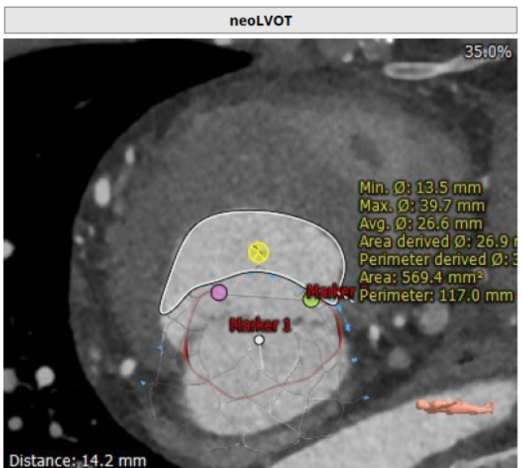

术前CT:收缩期NeoLVOT

术前CT:瓣环直径